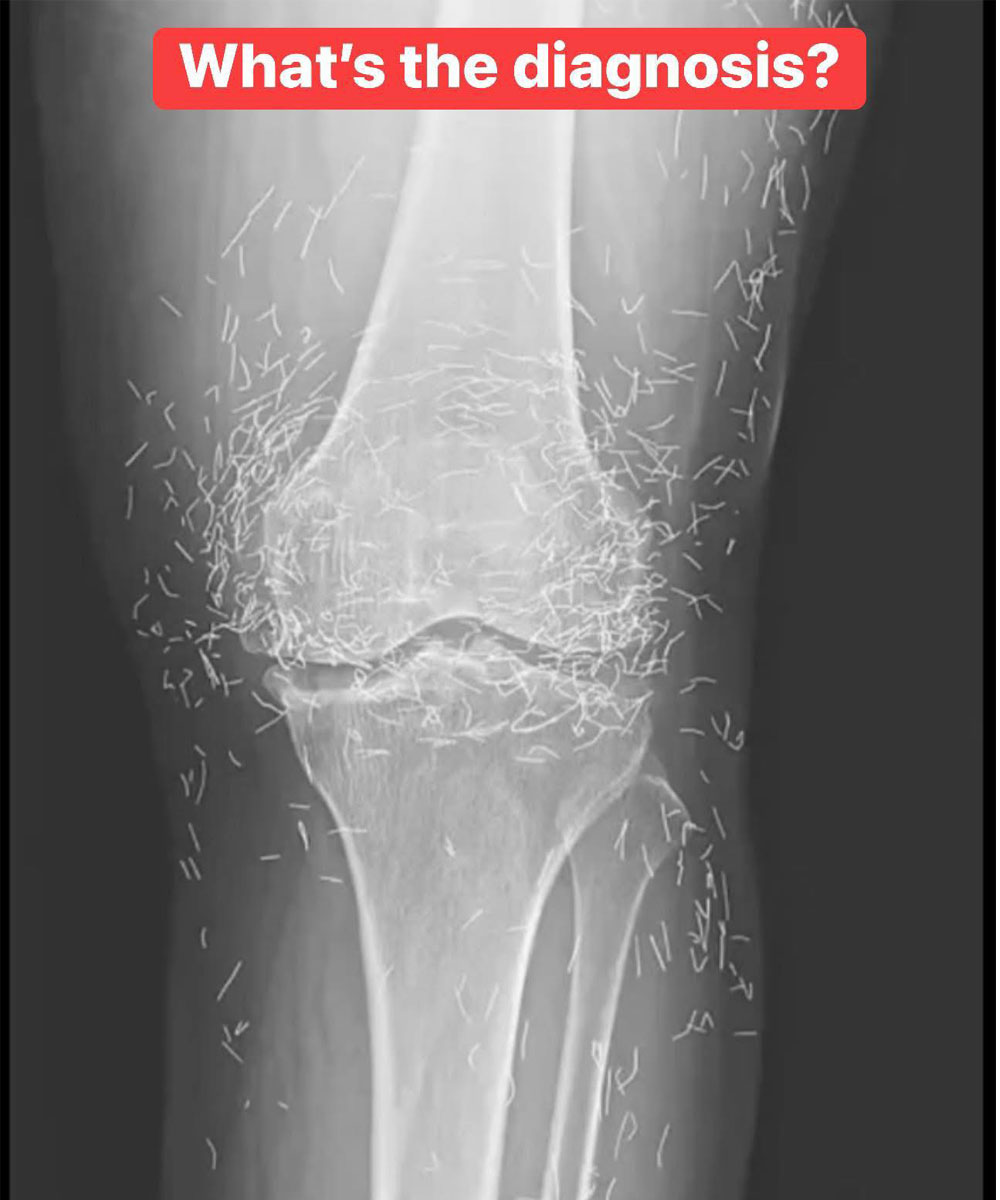

X-Ray Reveals Hundreds of Gold Needles in Woman’s Knees

As doctors examined an X-ray image of the knees of an old woman experiencing severe joint pain, they found a gold mine: hundreds of tiny gold acupuncture needles left in her tissue.The 65-year-old woman from South Korea had previously been diagnosed with osteoarthritis, a condition in which the cartilage and bones within the joints degrade,…